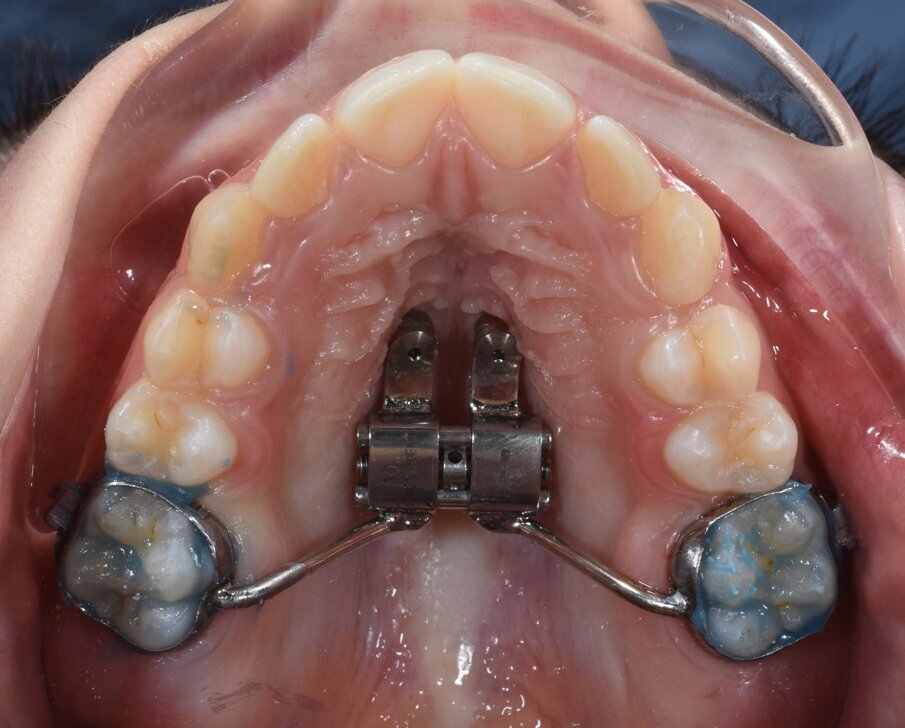

In questo stadio la fusione della sutura è già avvenuta parzialmente o totalmente, ed è quindi stata eseguito una MARPE. È stata progettata una dima CAD/CAM, mediante protocollo Easy Driver5. La CBCT è stata sovrapposta alla scansione digitale STL (standard triangulation language) dell’arcata dentale superiore, per valutare con estrema precisione il sito più adatto di inserimento, la lunghezza e il diametro delle viti, rispettando la profondità della volta palatina, e l’inclinazione di inserimento delle viti (Fig. 4).

È stata quindi prodotta una dima guida, prodotta con la tecnica additive manufacturing. La dima contiene tutte le informazioni programmate digitalmente per l’inserimento di 2 miniviti BENEfit di 9 mm di lunghezza e 2 mm di diametro. In un’unica seduta sono state posizionate TADs ed espansore palatale ibrido. Il protocollo di attivazioni eseguito ha previsto 5 attivazioni al momento dell’inserimento dell’apparecchiatura, e successivamente 1 attivazione al giorno per 20 giorni. Una volta corretta la trasversalità, il caso è stato finalizzato mediante terapia ortodontica con brackets su entrambe le arcate. Le miniviti e l’espansore rapido palatale sono rimaste in sede per tutta la durata della terapia ortodontica, di circa 20 mesi (Figg. 5a-5d). L’espansione scheletrica mascellare ottenuta è stata di 5,6 mm, evitando compensi dentali sui primi molari (Figg. 6a, 6b).

Fig. 5a_Inserimento miniviti.

Fig. 5b_Applicazione in un’unica seduta di espansore palatale ibrido ad appoggio dentale e scheletrico.